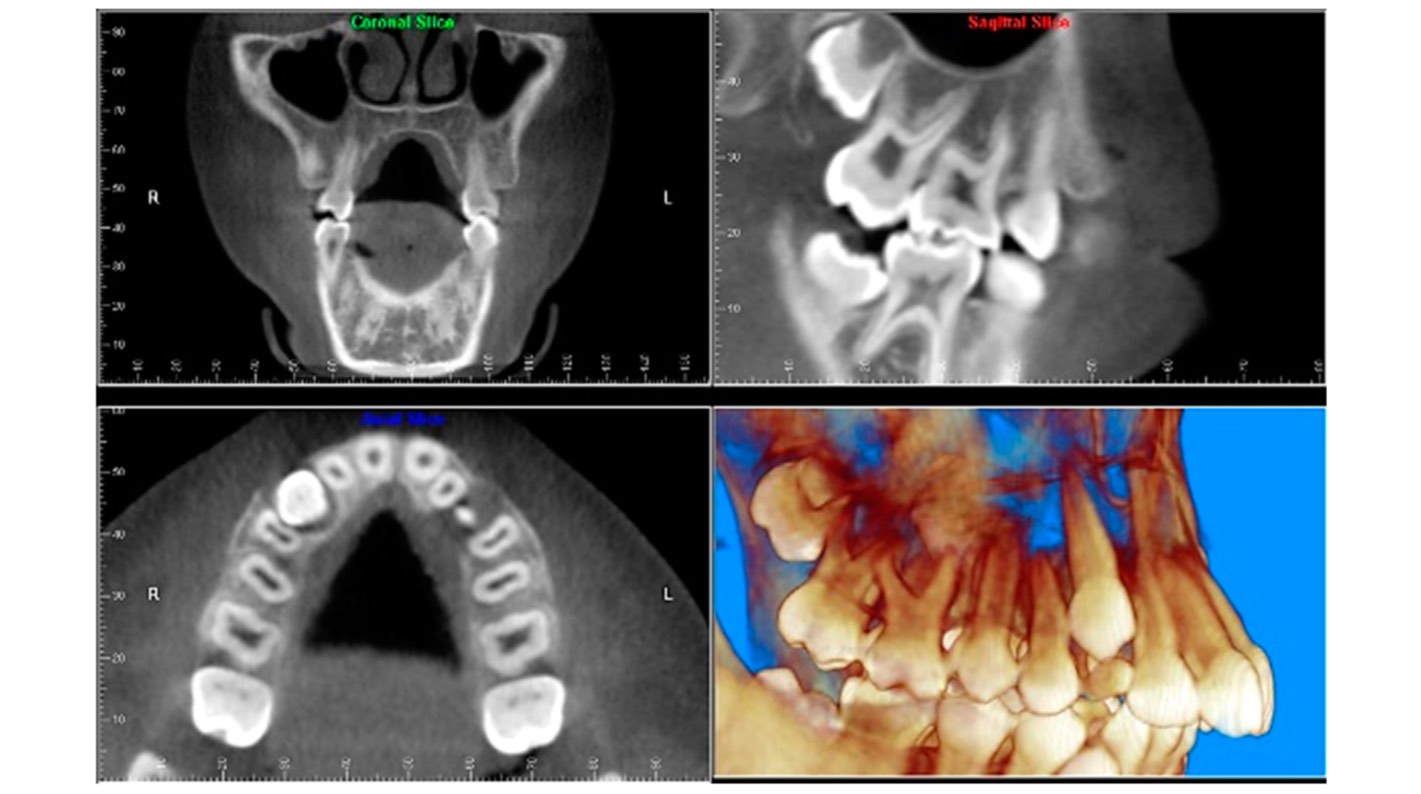

Si tu campo de trabajo es la endodoncia, un escáner CBCT puede aportar la visión axial, coronal y sagital que no puedes obtener con la radiología convencional, aunque esta sin duda es más práctica y adecuada para los procedimientos más habituales en endodoncia. El CBCT tiene gran ventaja en eliminar o reducir la superposición de las estructuras, por ejemplo, para:

Visualizar la anatomía de los conductos radiculares: si utilizas un escáner CBCT con un limitado FOV podrías reconocer con mayor precisión los canales radiculares y aportar mediciones más exactas de las angulaciones de las raíces.

Identificar una patología periapical: con un equipo CBCT se obtendría mayor sensibilidad en el diagnóstico de lesiones periapicales experimentales, sin embargo, no debemos olvidar los artefactos del material restaurador que podrían dificultar el diagnóstico.

Identificación de fracturas en dientes: el escáner CBCT supera a la radiología convencional en el diagnóstico de fracturas dentarias ya que salvo que el haz de rayos esté orientado de modo que atraviese el plano de la fractura, en una radiografía intraoral no es posible separar los fragmentos en la imagen. Nuevamente, este diagnóstico en CBCT se podría ver perjudicado por los artefactos.

Análisis del proceso de reabsorción radicular interna y externa: con tu equipo CBCT podrás no solamente detectar la ubicación exacta, sino que también determinar la extensión de la reabsorción y la comunicación con el espacio del ligamento periodontal.